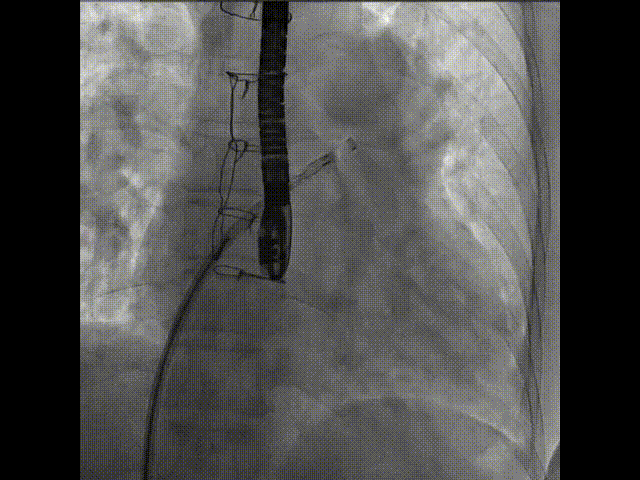

術中首先在局麻下穿刺股動脈、股靜脈,完成心導管檢查評估后轉為全麻,在食道超聲引導下穿刺房間隔,穿刺成功后將加硬導絲送入左上肺靜脈建立軌道,根據患者病情行球囊預擴張后植入6mm孔徑房間隔造孔支架,經透視及食道超聲評估支架左右盤展開良好,夾持于房間隔兩側,固定穩定、位置良好,食道彩超顯示房水平右向左為主分流,分流孔直徑符合預期大小,心導管檢查評估達到預期效果,釋放造孔支架。術后12h患者下床活動,恢復順利,擬于近日完善術后評估后出院。